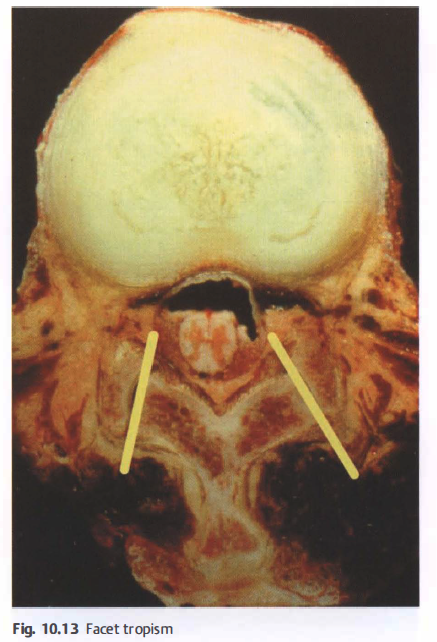

The L5/S1 joint facets orient themselves more in the frontal plane, somewhat increasing this segment's ability to axially rotate. The principle of anatomical variation continues in the lumbar ZAjs joint surfaces of the same level can be shaped differently with different spatial alignment without being pathological. Individual differences in the shape of the ZAjs between sides is labeled " facet tropism" (Jerosch and Steinleitner, 2005 ) ( Fig. 1 0.13).

- 후관절 굴성(facet tropism)

This means that the previously described spatial alignment of the joint surfaces is to be understood as only representing the average and that there are differences between the left and right side in each segment.

참고) facet tropism